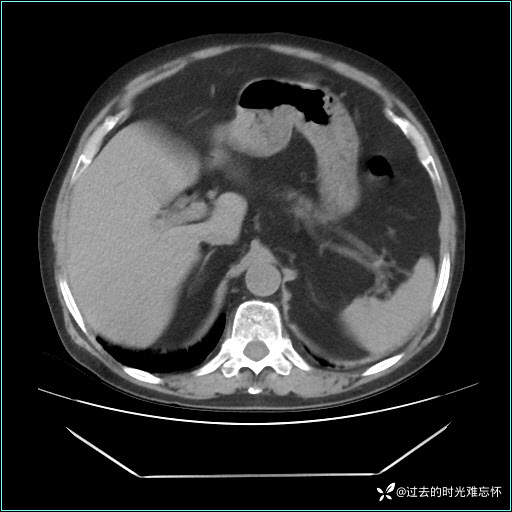

男子肚子大如孕晚期,一看腹腔竟被脂肪填满了...

患者男,71 岁,因「反复腹痛腹胀 1 月」入院。

现病史:患者 1 月前无明显诱因下出现腹痛腹胀症状,腹痛呈隐痛,当时未予以重视,后症状有所加重,常在进食辛辣刺激油腻等食物后出现腹痛,口服药物治疗症状能得到控制,病情控制一般。现为求诊治来我院,拟“腹痛”入院。病程中患者神志清楚,精神一般,无咳嗽咳痰,无恶心呕吐,近期体重无明显变化。